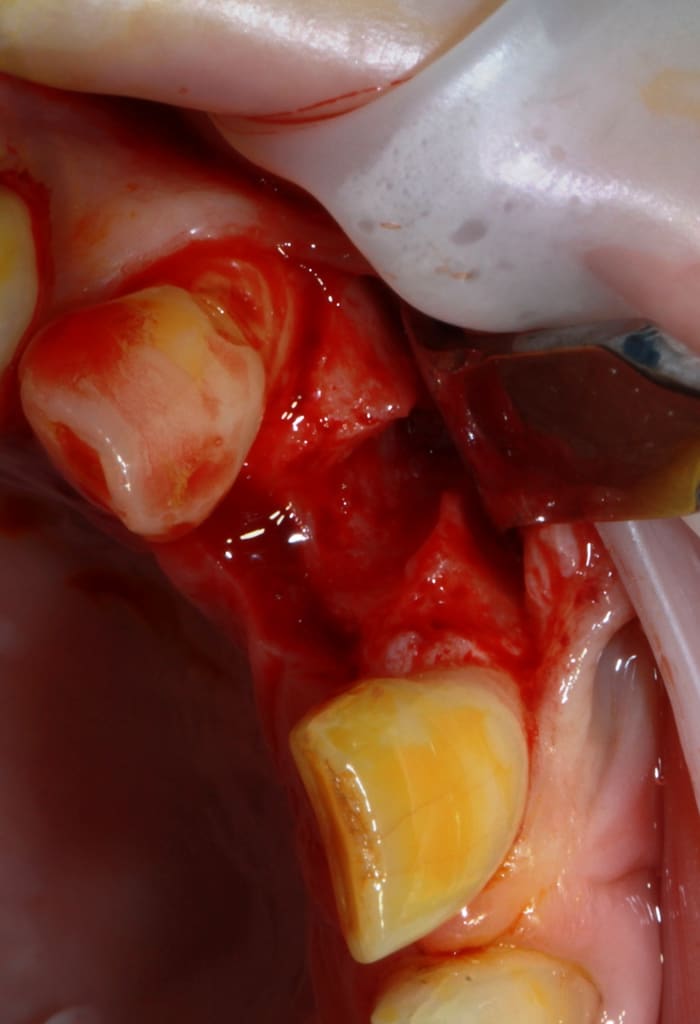

Thomas, tu as un plan pour guider dans un cas comme ça?

ou comment remplacer 12 avec soucis vestibulaire, par un implant, sans greffe, sans ROG, juste avec les mimines....?

vue de l’intérieur..